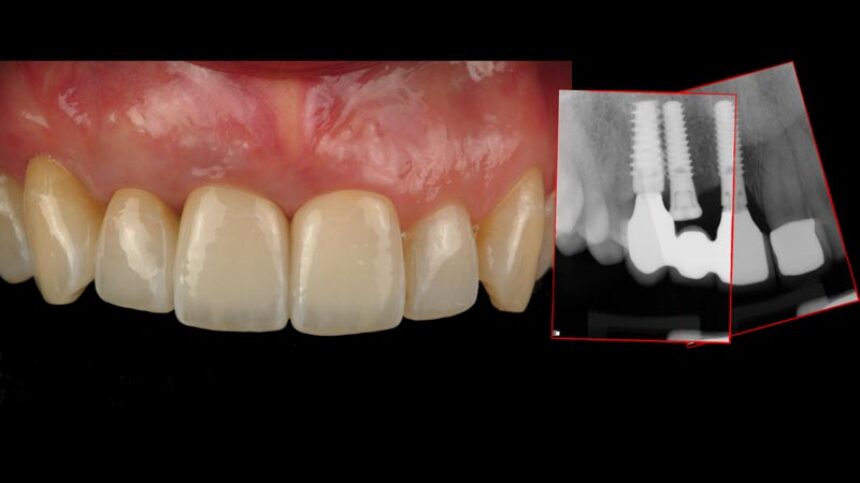

Understand the importance of CTG around dental implants for long term results

Techniques and tools to ensure predictable surgical & prosthetic results

Decision making process for the right treatment selection option

Managing failures with implants in the esthetic area, the options.